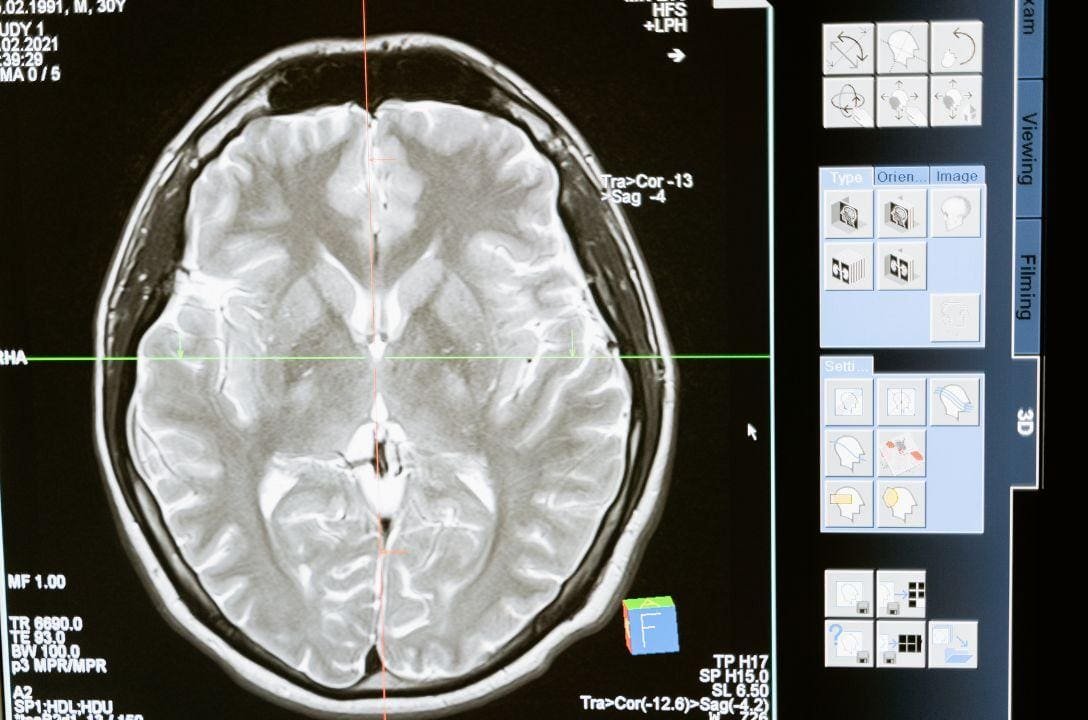

Mesmo que você não tenha contraído Covid-19, seu cérebro pode ter sido profundamente afetado. Um estudo publicado na revista Nature Communications revelou que o simples fato de viver sob o estresse da pandemia, com isolamento social, incertezas econômicas e mudanças abruptas na rotina, pode ter acelerado o envelhecimento cerebral de milhares de pessoas. E o mais curioso: isso foi detectado por imagens de ressonância magnética em pessoas saudáveis.

As alterações foram mais evidentes em homens, idosos e pessoas com menor renda. Mas não pense que os efeitos foram sutis. A pesquisa observou mudanças estruturais no cérebro comparáveis ao envelhecimento natural de alguns anos. Isso quer dizer que muitos de nós ficamos “mentalmente mais velhos” em tempo recorde, sem sequer perceber.